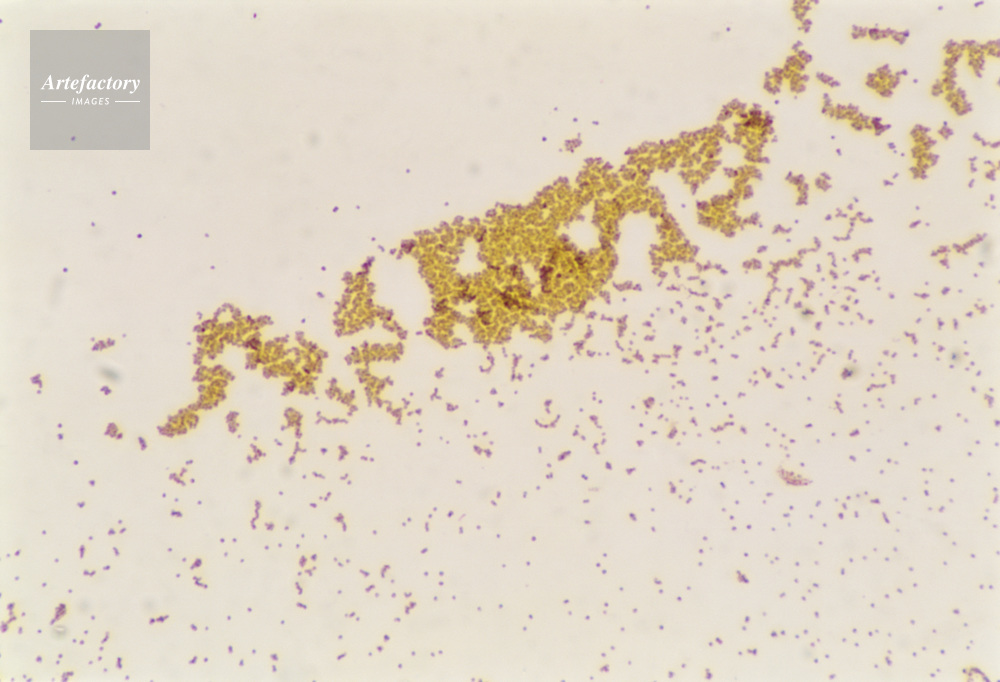

| 作品タイトル | 顕微鏡写真 | モデルリリース | なし | |

| キャプション | ぶどう状球菌,400倍 | 制限事項 | ||